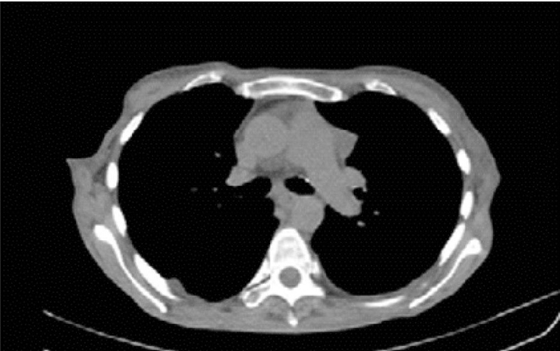

La paciente fue enviada 5 meses después a gastroenterología para descartar cáncer gástrico. Como parte del protocolo prequirúrgico para la realización de endoscopia se observó ensanchamiento mediastinal en la telerradiografía de tórax (Figura 1). El reporte histopatológico de la biopsia de estómago fue atrofia, engrosamiento de la capa muscular e infiltrado linfoplasmocitario, sin cambios compatibles con cáncer. En la tomografía toracoabdominal (Figura 2) se confirmó la tumoración en mediastino anterior. Fue sometida a toracotomía, donde se identificó un tumor mediastinal anterior de 8 a 10 cm, clasificado como timoma B1, con invasión a pericardio parietal y rama pulmonar izquierda.

Figura 2 Tomografía axial computarizada de tórax. Tumoración mediastinal anterior, con discreto derrame pleural derecho.